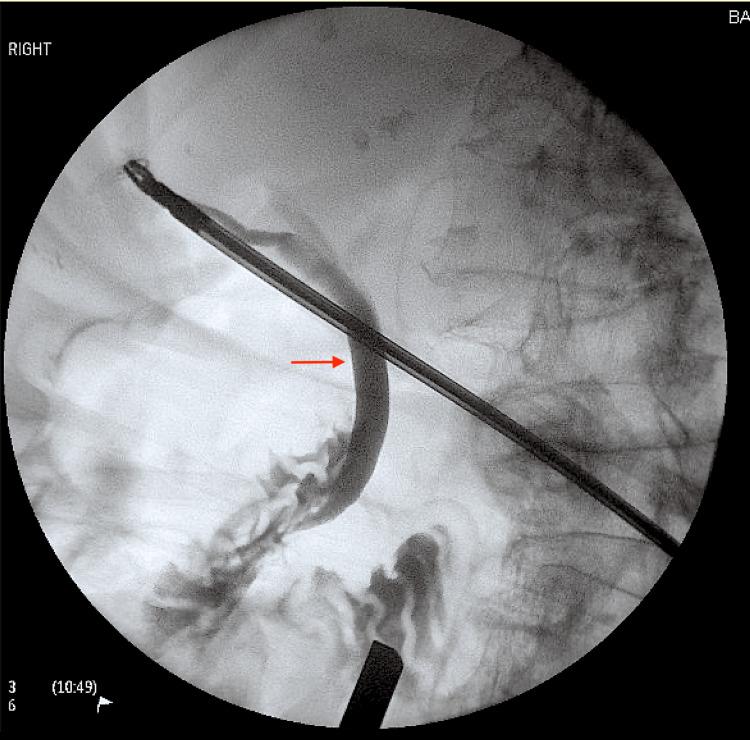

一名患有严重脊柱后凸侧弯的老年女性的胆囊扭转

Gallbladder volvulus is a very rare complication of a congenital defect in gallbladder development also known as a "floating" gallbladder and often presents in the elderly. Proposed aetiologies include loss of abdominal fat and kyphoscoliosis. We present a patient with severe lumbar scoliosis centred on L2, producing a lumbar vertebral distortion of about 30 degrees concave to the right, resulting in right hemiabdomen volume loss. The mechanical interaction between the gallbladder fundus and compressed viscera transmits abnormal ambulatory forces from the distorted right pelvic brim into the abdomen predisposing to gallbladder torsion. Laparoscopic cholecystectomy was performed without complication and the patient had an uneventful recovery. This case demonstrates the challenges of diagnosing gallbladder torsion preoperatively. A high level of clinical suspicion is vital especially in elderly patients to enable timely surgical intervention to reduce morbidity and mortality.

胆囊扭转是胆囊发育先天性缺陷的一种非常罕见的并发症,也被称为“漂浮”胆囊,且常发生于老年人。推测的病因包括腹部脂肪减少和脊柱侧凸。我们报告一例以L2为中心的严重腰椎侧凸患者,导致腰椎椎体向右凹陷约30度的变形,致使右半腹容积减小。胆囊底部与受压内脏之间的机械相互作用将来自变形的右骨盆边缘的异常活动力传递至腹部,易引发胆囊扭转。行腹腔镜胆囊切除术,无并发症发生,患者恢复顺利。该病例显示了术前诊断胆囊扭转的挑战。尤其是对老年患者,高度的临床怀疑至关重要,以便能及时进行手术干预,降低发病率和死亡率。